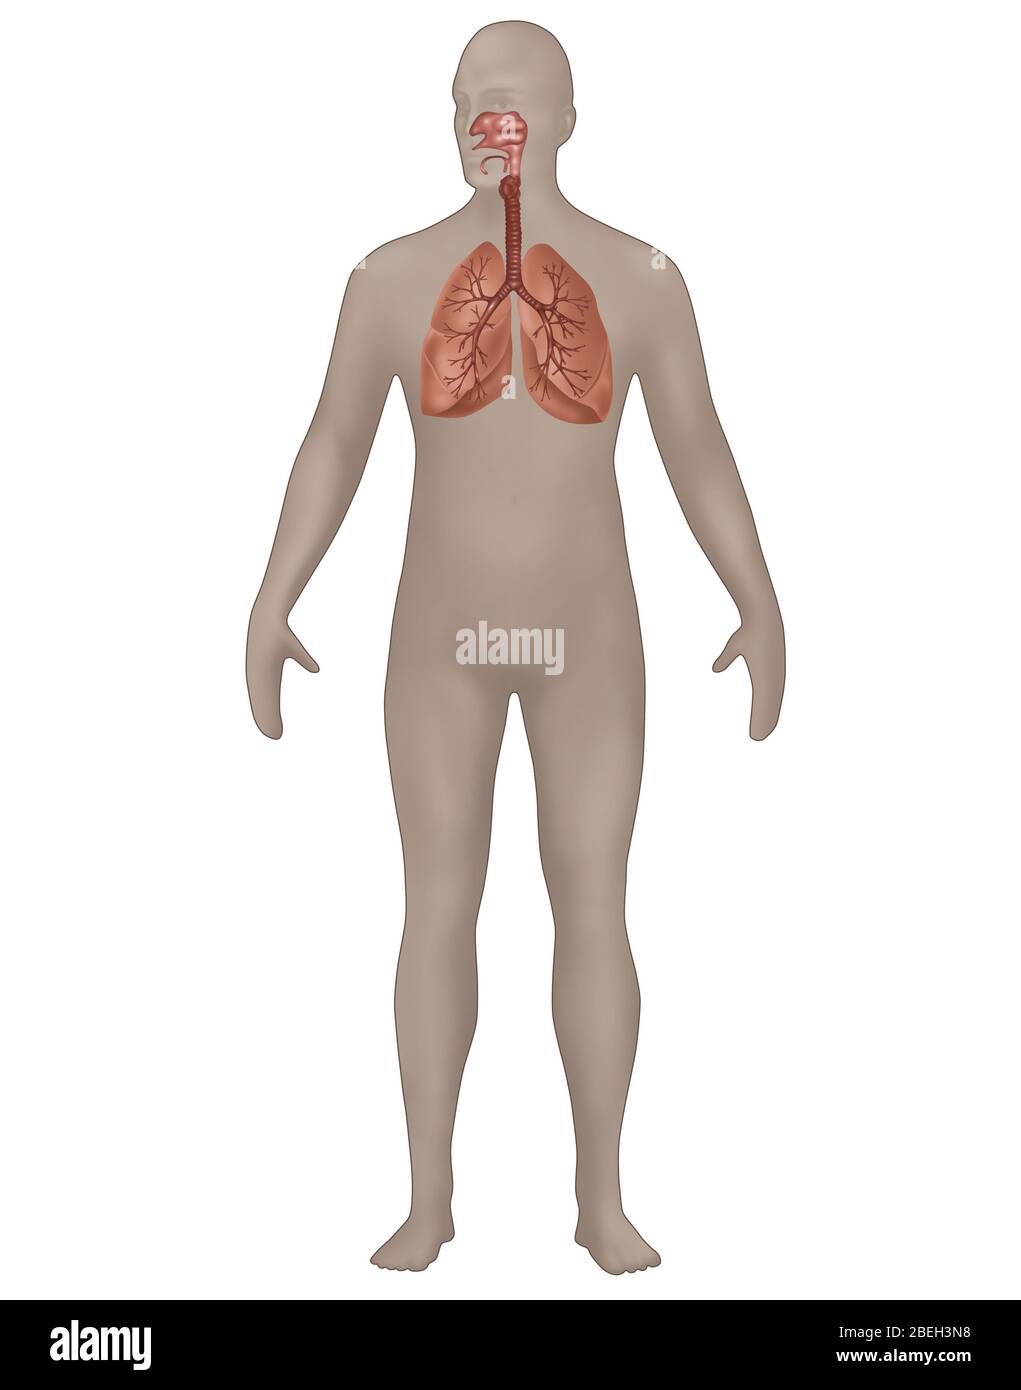

RFPAYTH0–Innere Organe, männlichen Körper - schematische Darstellung der menschlichen Anatomie Illustration - auf weißem Hintergrund.